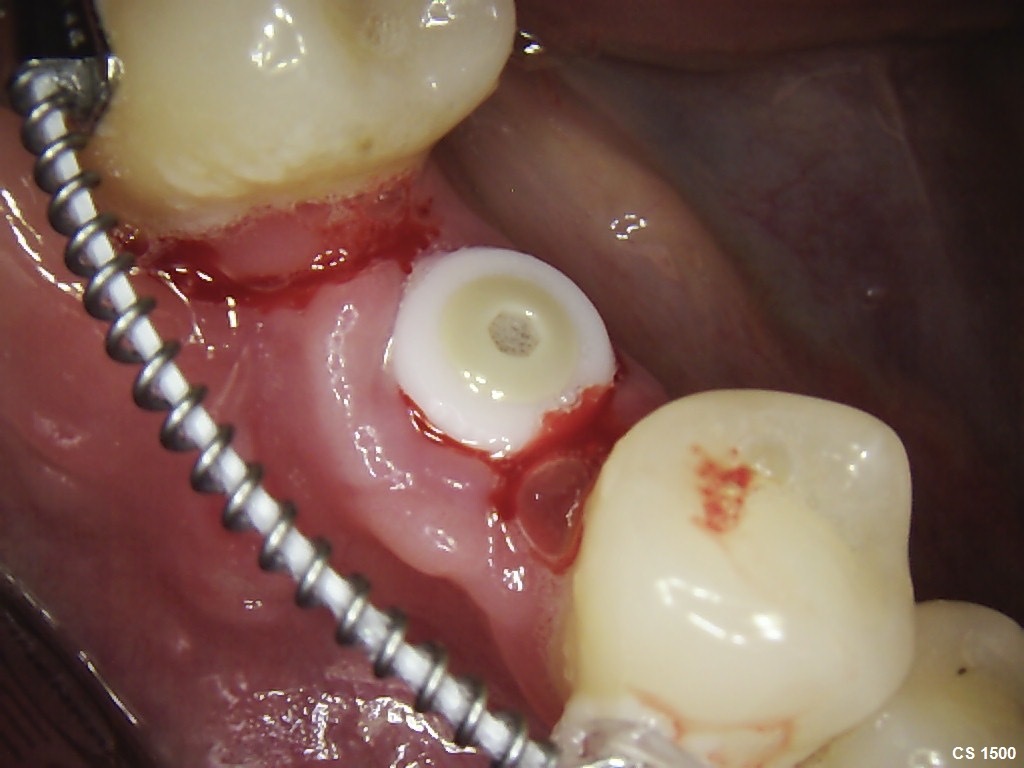

After 6 months of successful

orthodontic treatment, we were finally able to place the implant and the

provisional crown. After 4 months of ingrowth, aligners were removed and a full

ceramic crown was placed. The treatment was successfully completed!✋🏽😉